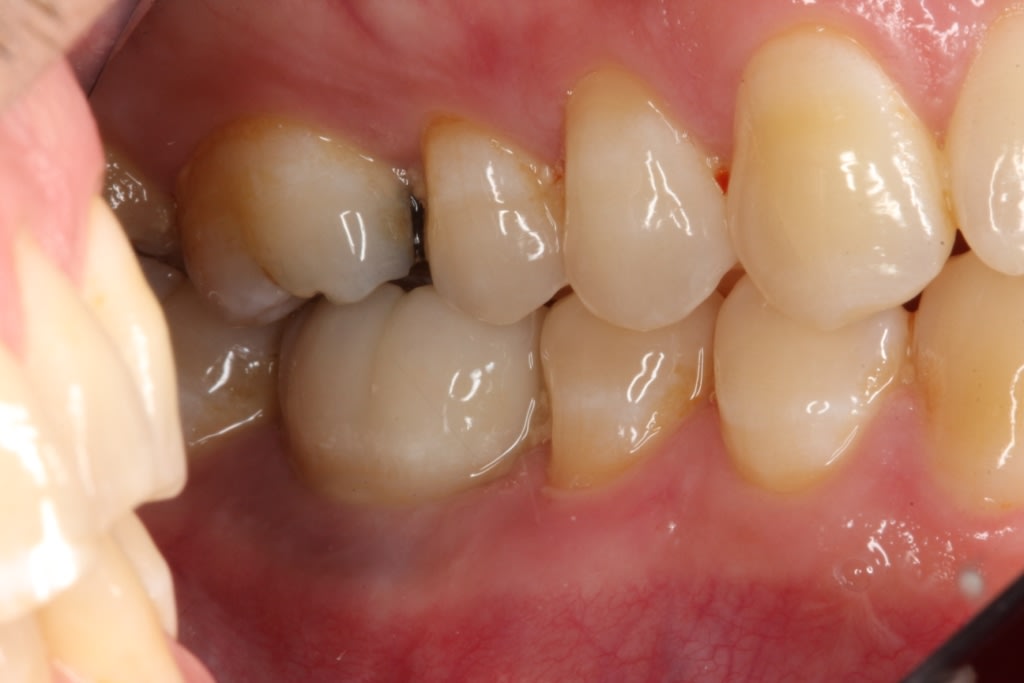

In July 2012 the stock abutment (using the standard platform-switched connection) and final porcelain-fused-to-metal (PFM) crown were placed; gingival health was excellent and showed a midfacial PD of 1 mm (Figure 7). At 18 months (Visit 7) a midfacial probing depth of 3 mm without bleeding was noted (Figure 8). Endodontic treatment was performed on tooth No. 5 after completion of the implant restoration (Figure 9). A subsequent follow-up photograph from January 2015 (Figure 10) shows the facial view of the final crown in occlusion.

Figure 15 shows the periapical radiograph at final crown placement (Visit 4). The abutment was screwed in place to a torque of 35 Ncm and the cement-retained crown was placed with RelyX™ Unicem (3MESPE, www.3MESPE.com); at this time only mild gingival inflammation was observed (Figure 16). One year later (18-month follow-up), an excellent esthetic result was observed from the facial aspect, with good tissue tone and no gingival recession (Figure 17).

The midfacial PD at Visit 7 (18-month follow-up) was 2.5 mm, with no bleeding and good gingival tone (Figure 34). Good radiographic osseointegration (Figure 35) and excellent soft-tissue and restoration esthetics were observed at this visit (Figure 36 through Figure 38). The patient was last seen in February 2015 (almost 3 years after implant placement), at which time favorable hard- and soft-tissue levels and optimal esthetics were confirmed clinically and radiographically (Figure 39 and Figure 40).

Figure 47 shows the stock abutment connected to the implant prior to extraoral cementation to the final PFM crown, which was followed by screw-retained placement (Visit 4). Figure 48 shows a good emergence profile, good gingival health, and a PD of 1 mm approximately 3 weeks after cementation (6-month follow-up), and Figure 49 confirms excellent esthetics and good occlusion at the 18-month follow-up visit (Visit 7).